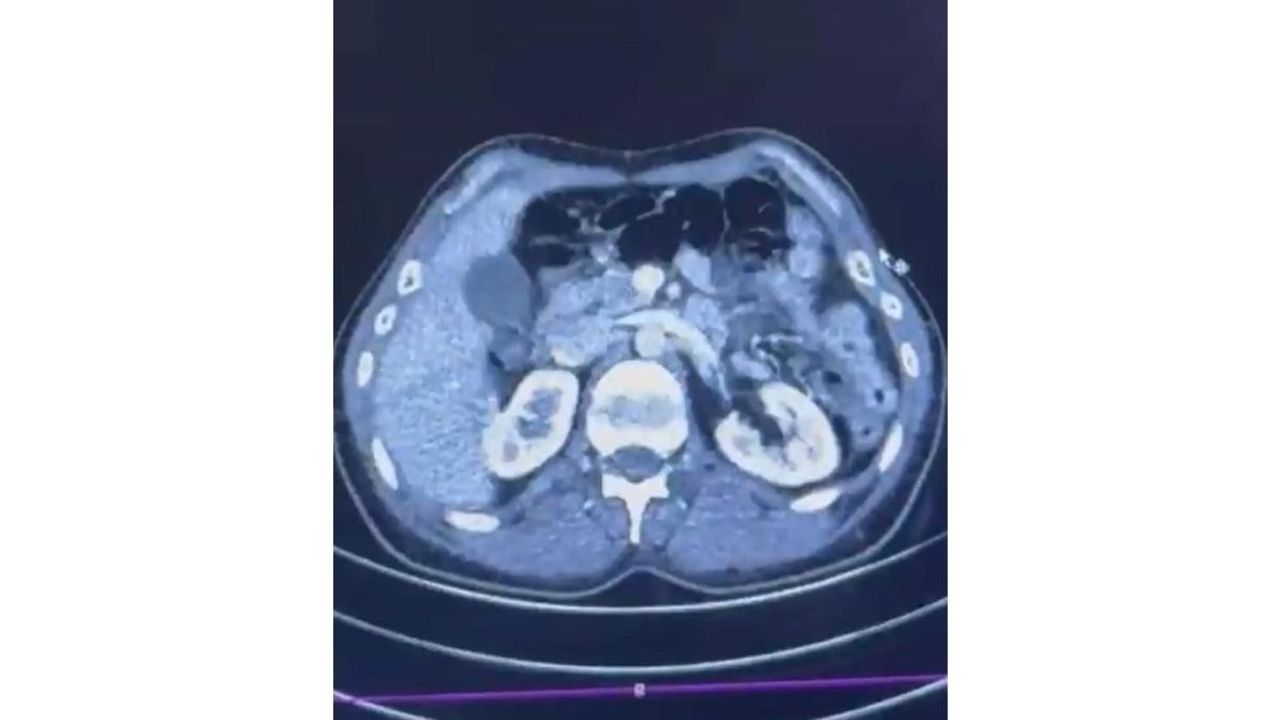

Düzenlenen operasyonda S.C., R.B.C. ve G.M. isimli şüpheliler gözaltına alındı. Şüphelilerden S.C. ve R.B.C.’nin Kayseri Şehir Hastanesi’nde yapılan iç beden muayenelerinde, mide kısımlarında kapsül halinde gizlenmiş 50 adet kapsül içerisinde toplam 554 gram metamfetamin ele geçirildi.